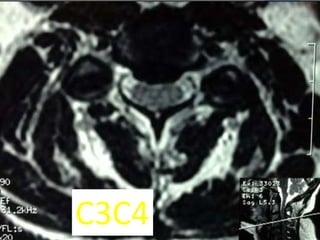

c3c4